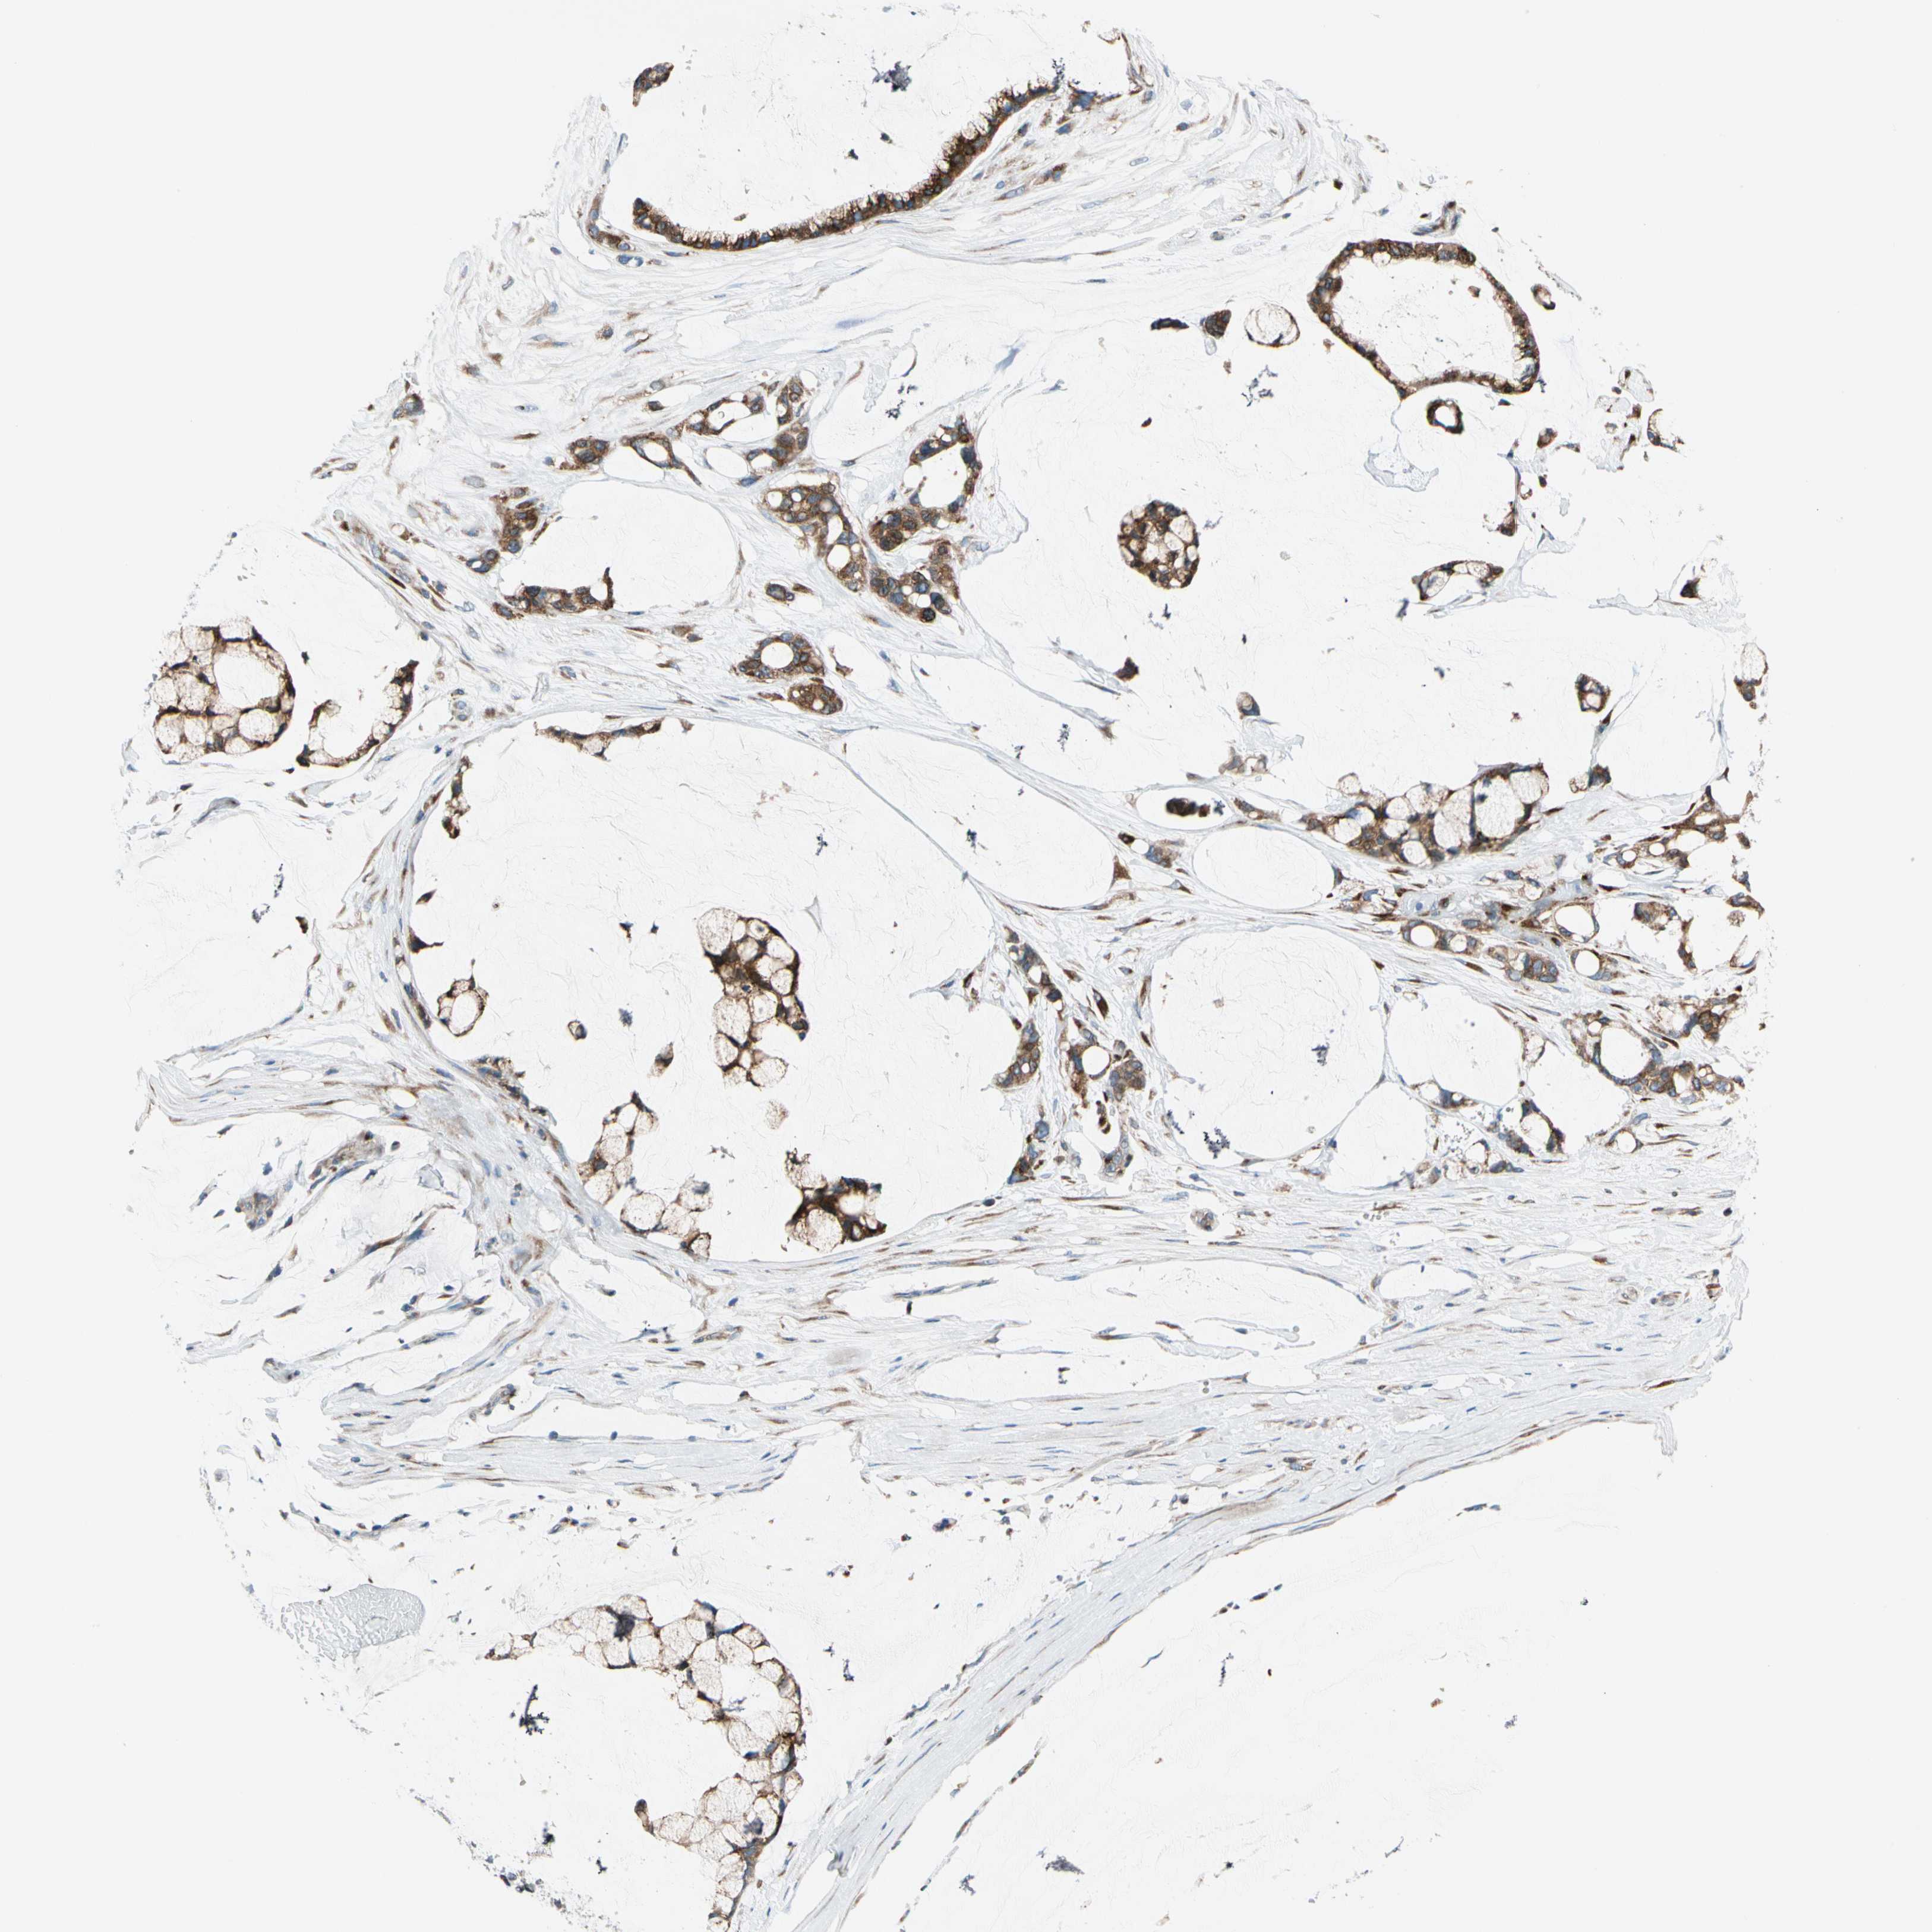

OVARIAN CANCER - Protein expressioni

A mouse-over function shows sample information and annotation data. Click on an image to view it in a full screen mode. Samples can be filtered based on level of antibody staining by selecting one or several of the following categories: high, medium, low and not detected. The assay and annotation is described here.

Note that samples used for immunohistochemistry by the Human Protein Atlas do not correspond to samples in the TCGA dataset.

Antibody stainingi

Antibody staining in the annotated cell types in the current human tissue is reported as not detected, low, medium, or high, based on conventional immunohistochemistry profiling in selected tissues. This score is based on the combination of the staining intensity and fraction of stained cells.

Each image is clickable and will lead to virtual microscopy that enables deeper exploration of all samples and also displays staining intensity scores, fraction scores and subcellular localization as well as patient and tissue information for each sample.

Antibody HPA008176

Staining

High

Medium

Low

Not detected

Intensity

Strong

Moderate

Weak

Negative

Quantity

>75%

75%-25%

<25%

None

Location

Nuclear

Cytoplasmic/membranous

Cytoplasmic/membranous,nuclear

Cystadenocarcinoma, serous, NOS

Carcinoma, endometroid

Cystadenocarcinoma, mucinous, NOS

Carcinoma, NOS